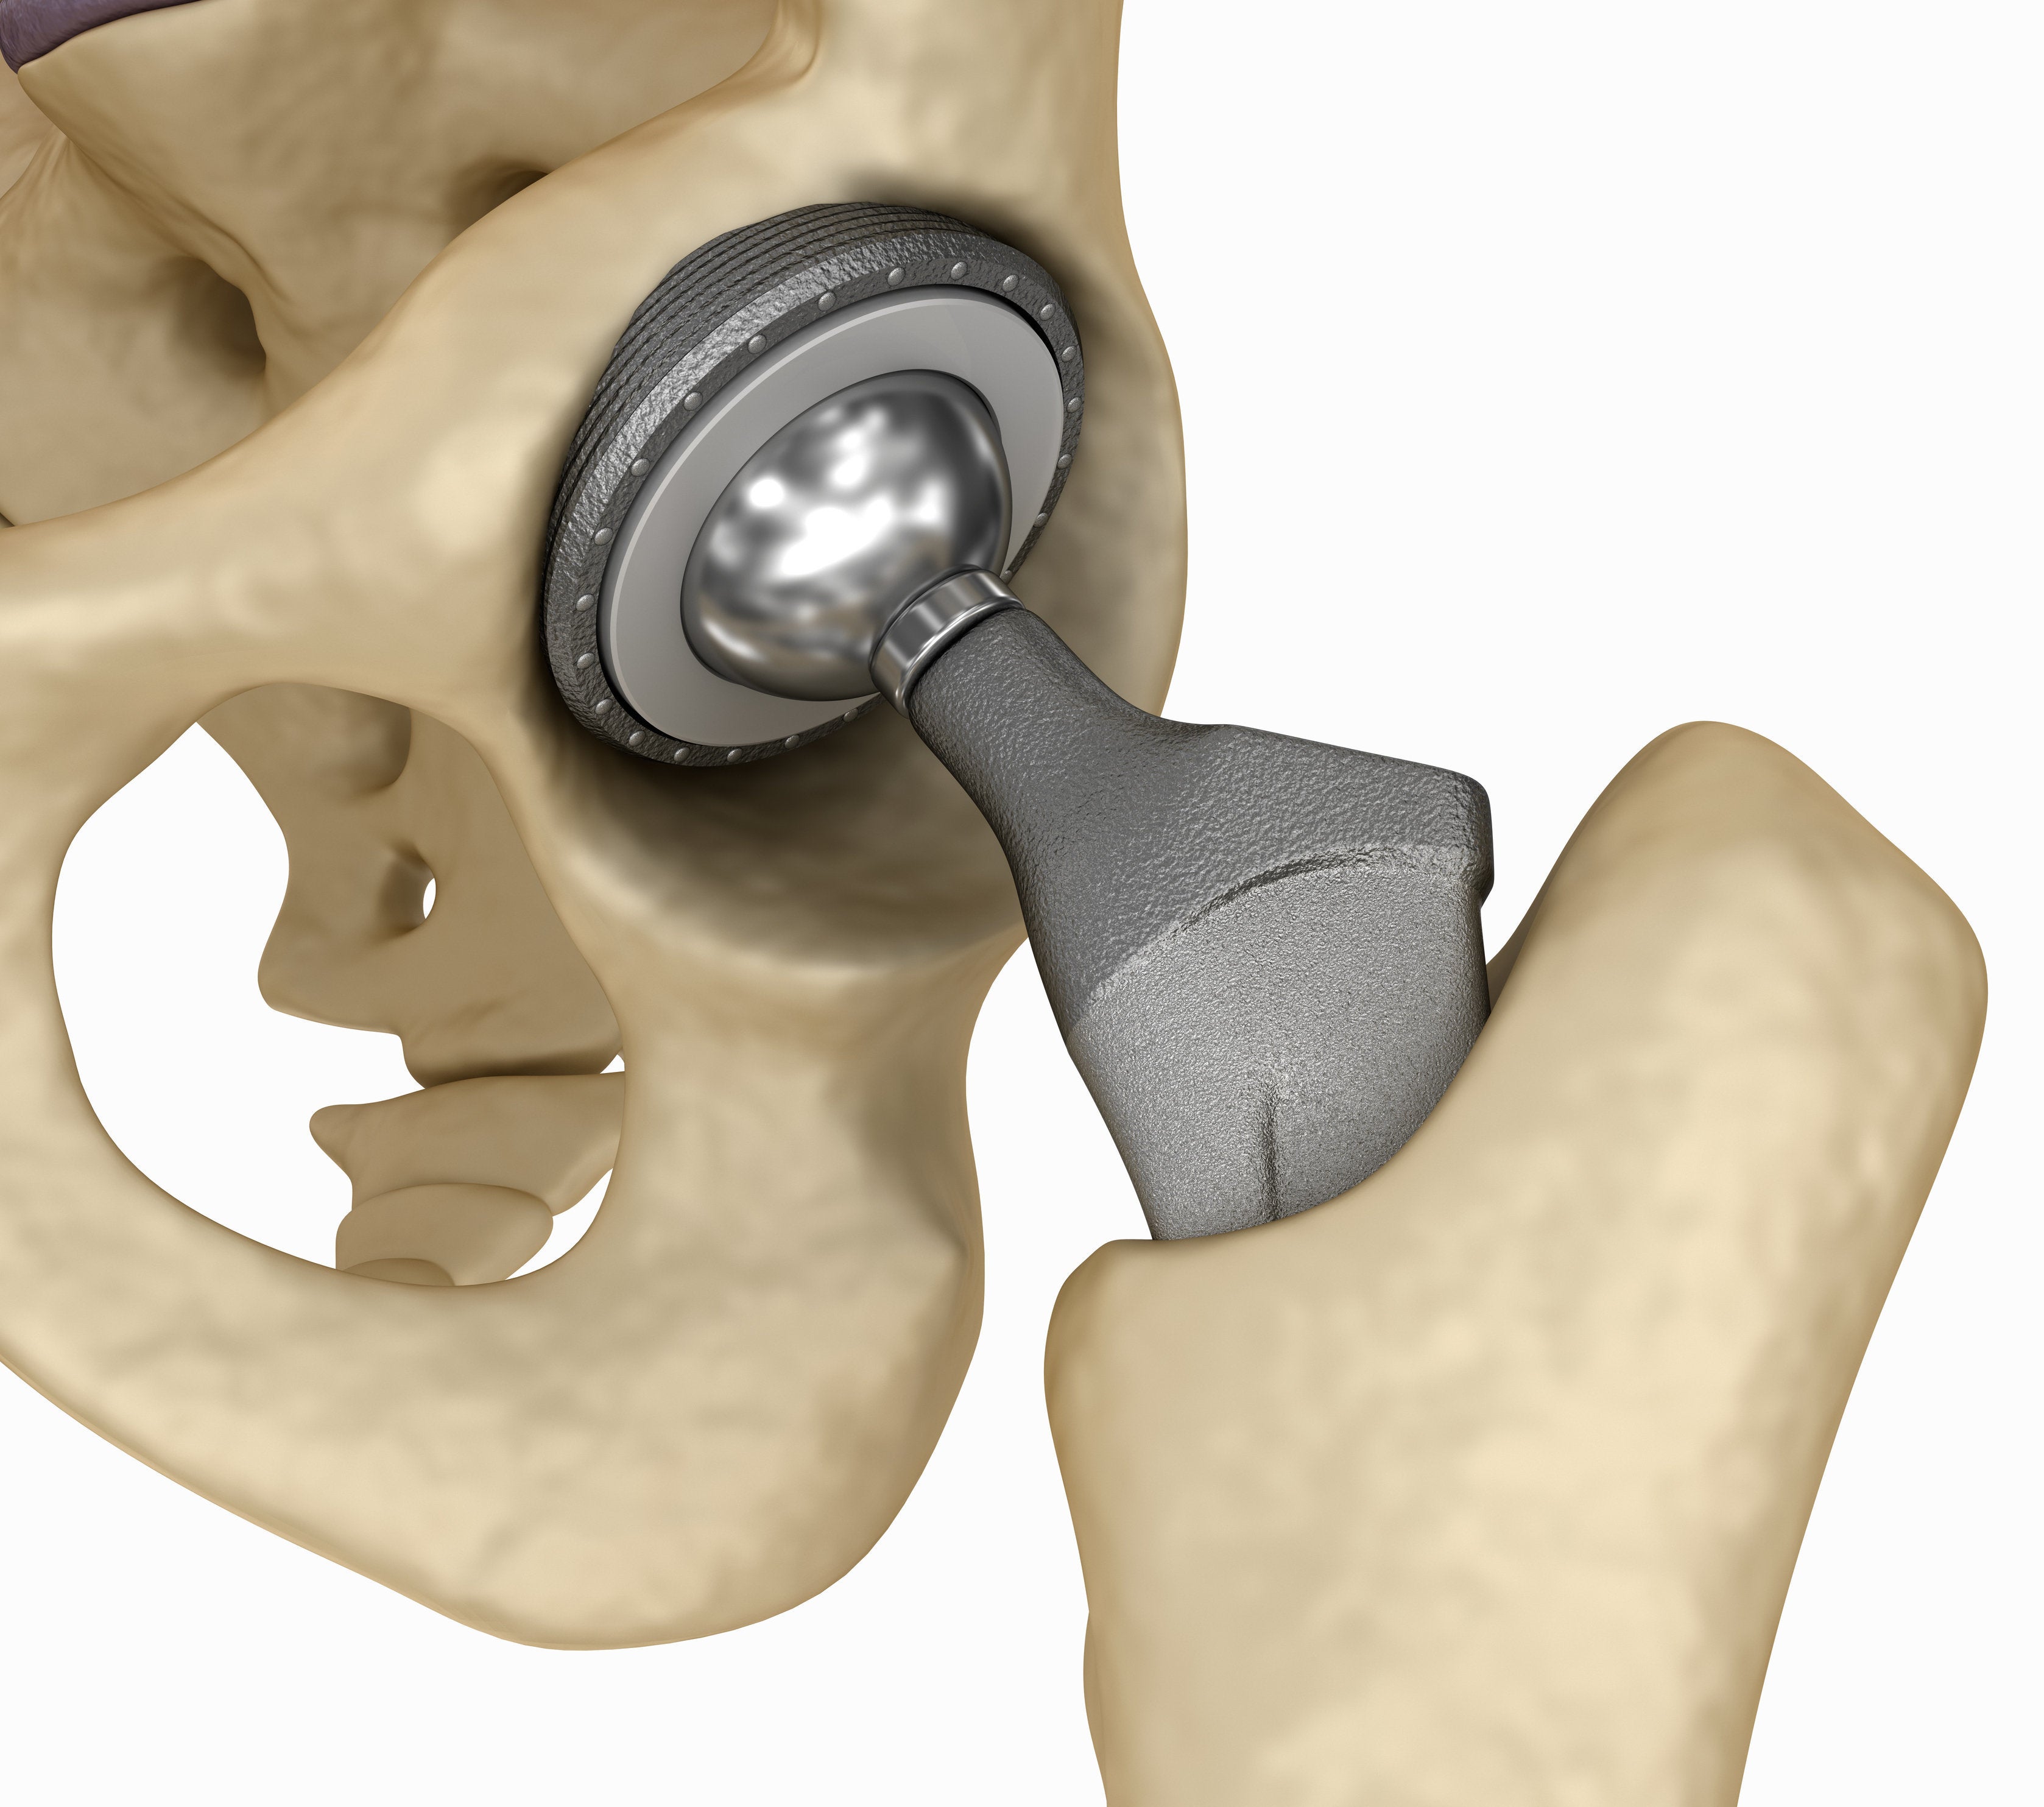

Замена таз сустава

Замена таз сустава 113 фотографий